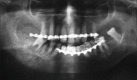

Chondrosarcomas are the malignant cartilaginous neoplasms rarely seen in the head and neck region. The chondrosarcomas may show an aggressive course and are mostly located in relation with anterior maxilla and base of the skull. Chondrosarcomas of the body of mandible are infrequent. We report a case of low-grade chondrosarcoma of body of mandible, which was treated with a simple excision without neck dissection.